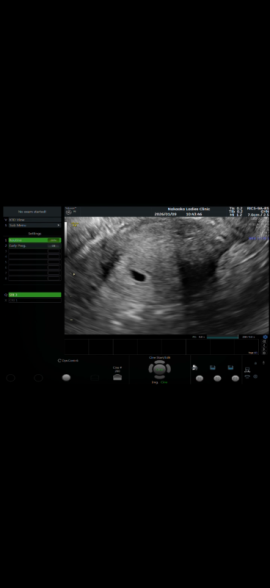

ご妊娠なさって最初は、赤ちゃんは小さいためエコーで確認することはできず、赤ちゃんがいるスペースである、胎嚢だけが見える状態です。通常ですと、7週くらいまでに胎嚢内に胎芽と言われる赤ちゃんが見えてくるようになりますよ。まだ6週ということであれば、もう少し経過を見て、胎芽が見えてくるようになれば、問題ないと思いますよ。